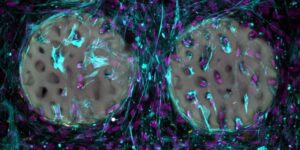

Shkencëtarët përdorin lazer për ta formuar materialin me saktësi shumë të lartë, duke krijuar struktura shumë të imëta që imitojnë rrjetin e brendshëm të kockës. Teknologjia lejon krijimin e formave me detaje deri në 500 nanometra dhe me shpejtësi shumë të lartë prodhimi.

Në laborator, qelizat që formojnë kocka u vendosën shpejt në këtë strukturë dhe filluan të prodhojnë kolagjen, një komponent thelbësor i indit kockor. Testet treguan gjithashtu se materiali është biokompatibël dhe nuk dëmton qelizat.